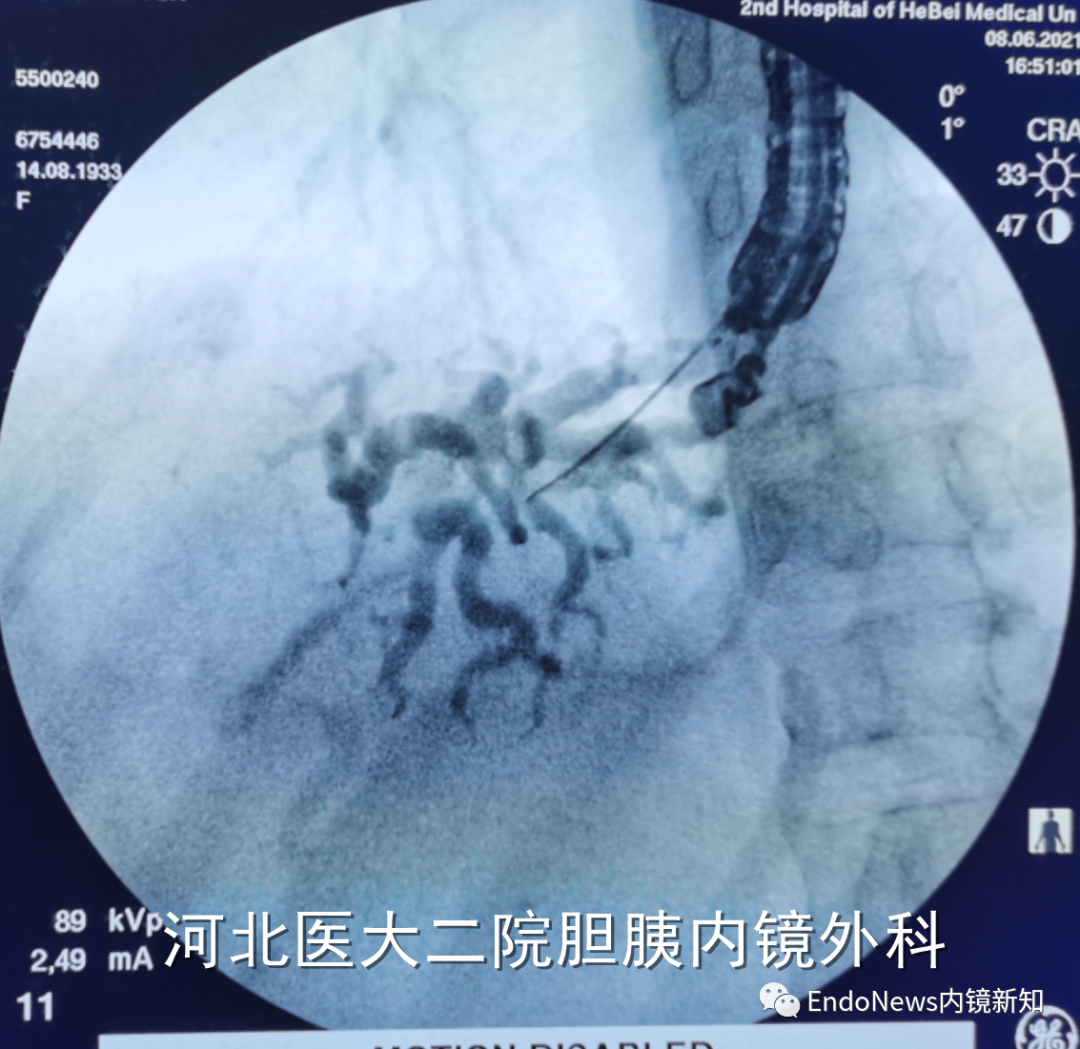

也有一些时候穿刺后导丝方向本身就是朝向胆总管下游方向的,比如下面两个病例:

如下图所示,肝门胆管狭窄(Bismuth IV型),导丝进入肝右叶胆管后就可以置入支架引流肝右叶胆管:

取石网篮 为什么贵EUS-BD操作中的细节:导丝如何超选?_https://www.jmylbn.com_新闻资讯_第14张